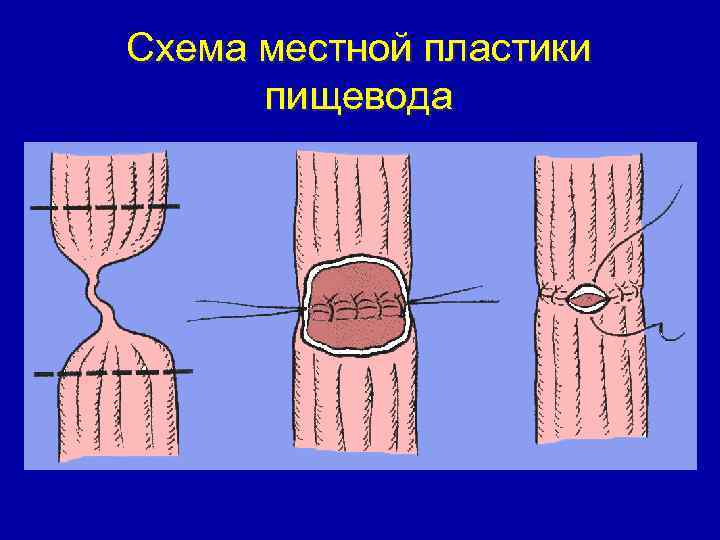

Резекция стриктуры с наложением анастомоза "конец в конец" Схема местной пластики пищевода.

Схема местной пластики пищевода